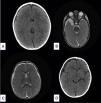

La aparición de un higroma subdural tras la rotura de la pared de un quiste aracnoideo es extremadamente infrecuente. Existen muy pocos casos descritos en la literatura. La mayoría de los casos se deben a una causa traumática. Su abordaje terapéutico, en aquellos casos sintomáticos, es controvertido, con una tendencia en la actualidad hacia el manejo conservador de forma inicial. En aquellos casos que precisen tratamiento quirúrgico existen múltiples opciones terapéuticas: se recomiendan las técnicas de fenestración como primera opción. Describimos 2casos tratados en nuestro centro, junto con una revisión de la literatura.

The appearance of a subdural hygroma after the rupture of an arachnoid cyst wall is extremely rare, with very few cases described in the literature. Most cases are due to a traumatic cause. The therapeutic approach in symptomatic cases is controversial, with a current tendency toward conservative management initially. In those cases that require surgical treatment, multiple therapeutic options are available, with fenestration techniques being recommended as first-line treatment. We describe 2cases treated in our centre and review the literature.